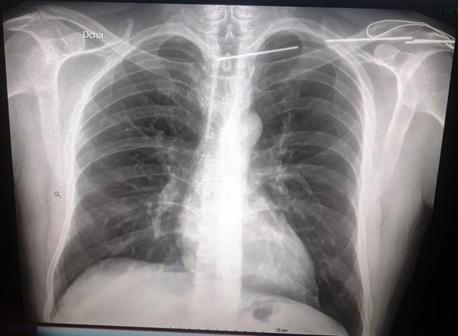

Turn static files into dynamic content formats.

Create a flipbook

Issuu converts static files into: digital portfolios, online yearbooks, online catalogs, digital photo albums and more. Sign up and create your flipbook.